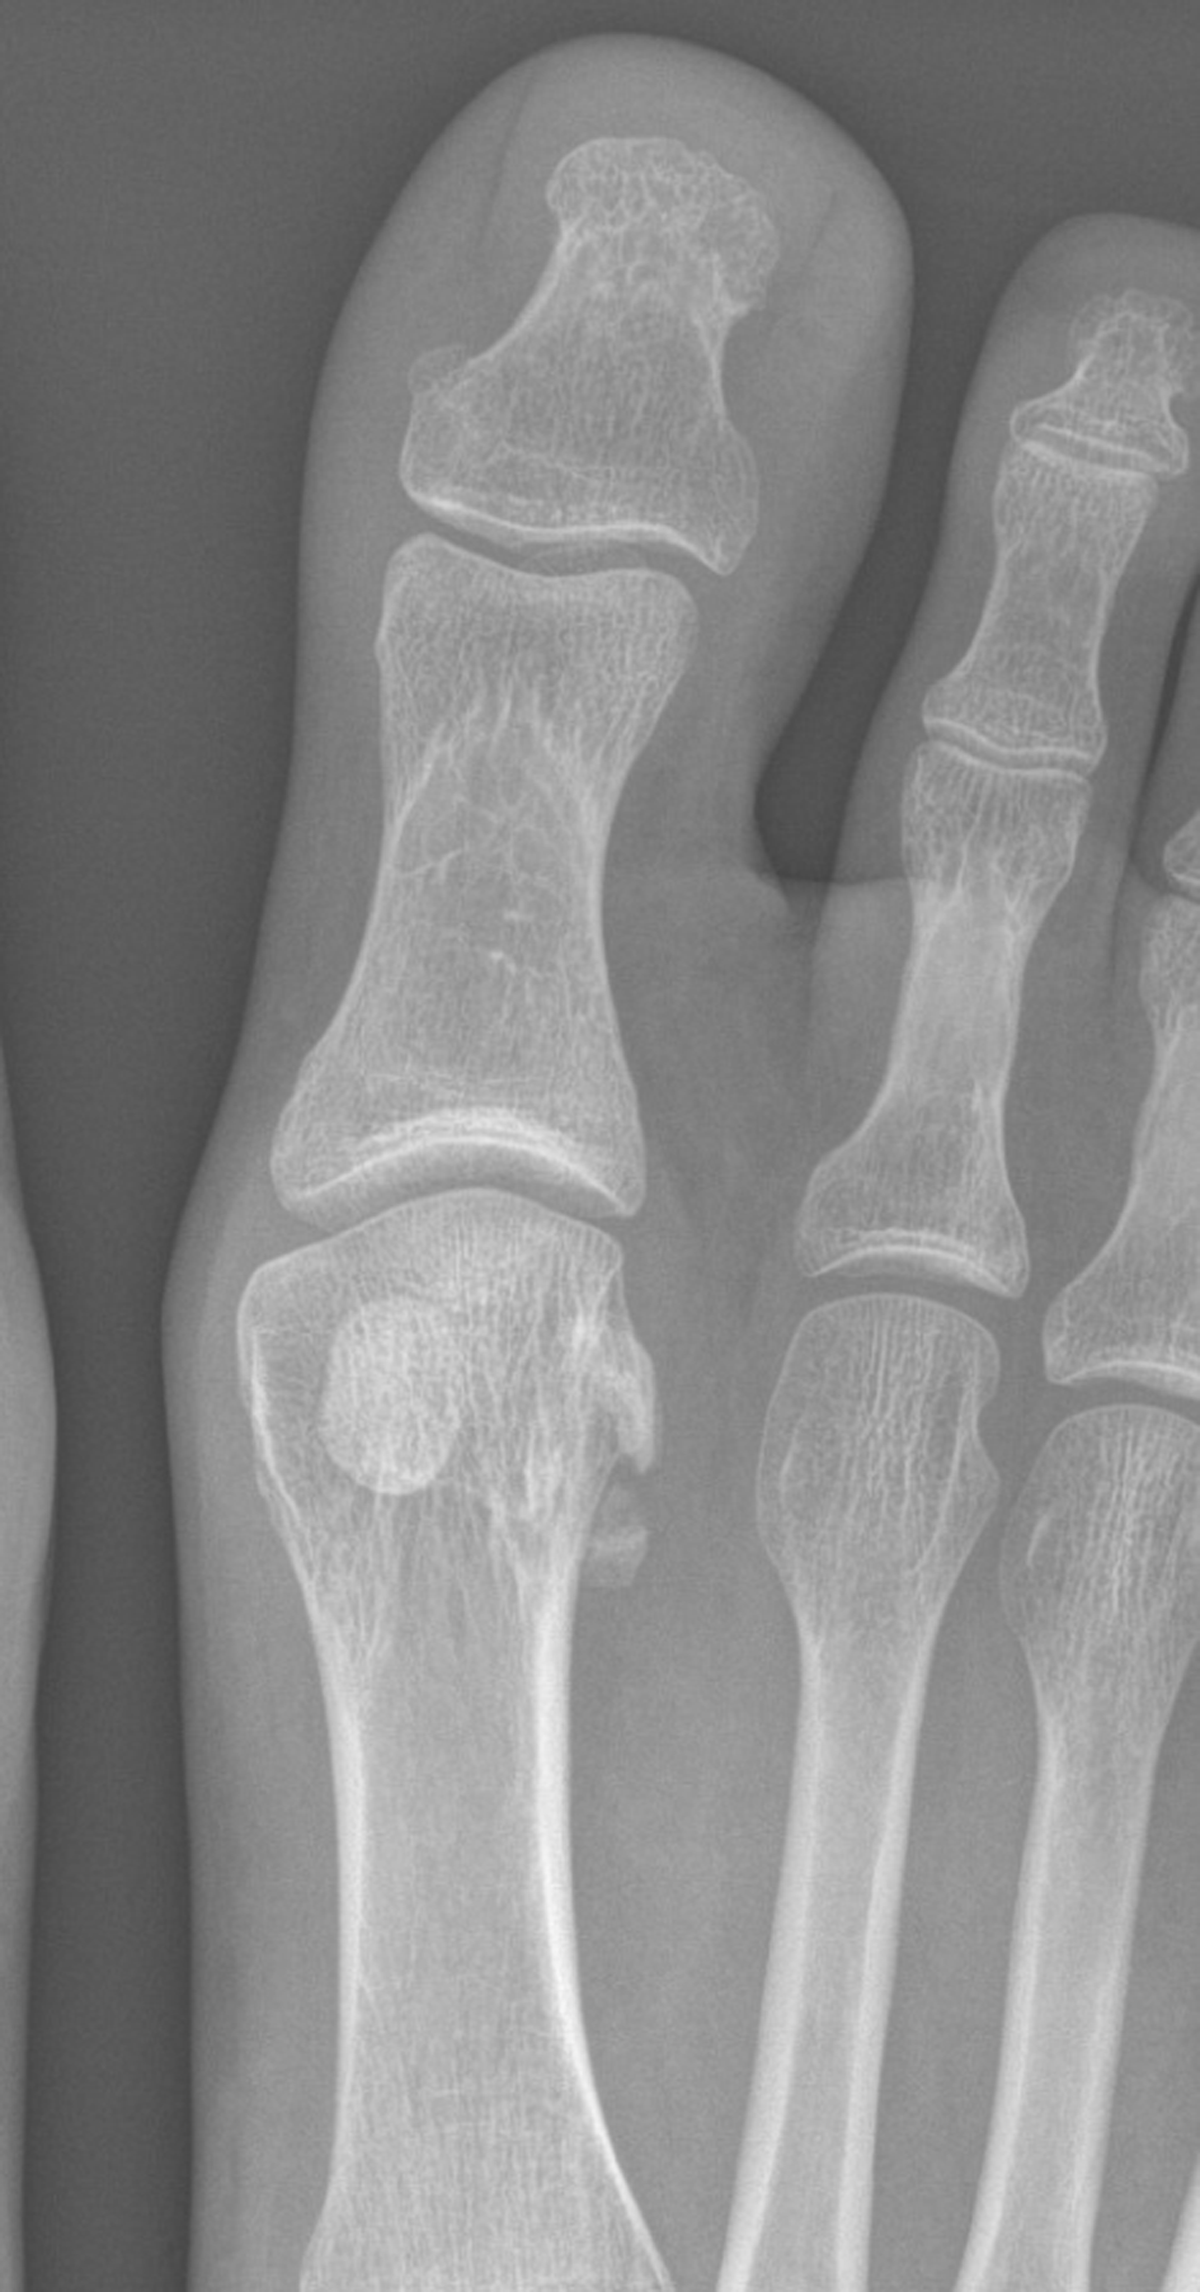

8. Turf toe

Lesions of the plantar plate system of the hallux most typically have been described in American football players. They also occur in sports such as volleyball, basketball, and sports involving jumping. The importance is to understand the normal anatomy of the hallux plantar plate including the sesamoids in order to diagnose these injuries. A fracture dislocation of the hallux sesamoids is also part of this spectrum (Figure 2).